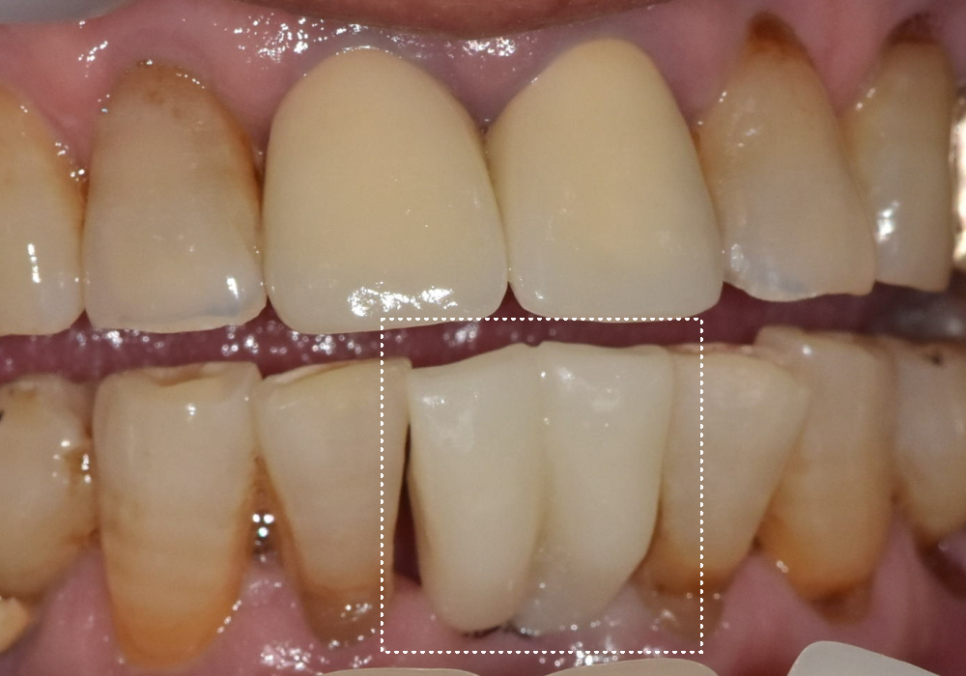

아래 앞니처럼 공간이 좁고,

힘이 비교적 덜 몰리는 부위에서는

조건에 따라 "2개"를 발치하더라도,

임플란트 "1개" 식립으로도

치료가 가능한 경우가 있습니다.

아래 앞니 2개 발치 후

임플란트 1개만 식립한 환자 사례

강동구 임플란트 가격 줄이는 방법

이 환자분은 아래 앞니가 흔들려

저희 병원에 내원하셨습니다.

241228

2개월 뒤 완성된 임플란트

2개 발치했는데, 1개만 심어도 된다구요? 강동구 임플란트 가격 줄이는 방법

약 2개월 뒤 보철이 완성됐고,

임플란트를 2개 심지 않더라도

아래 앞니 라인이

자연스럽게 정리되었습니다.

이번 케이스의 핵심은,

환자분의 비용 부담과

구조적, 기능적 안정성을 함께 고려해

무리 없는 설계로

과잉 수술을 줄였다는 점입니다.